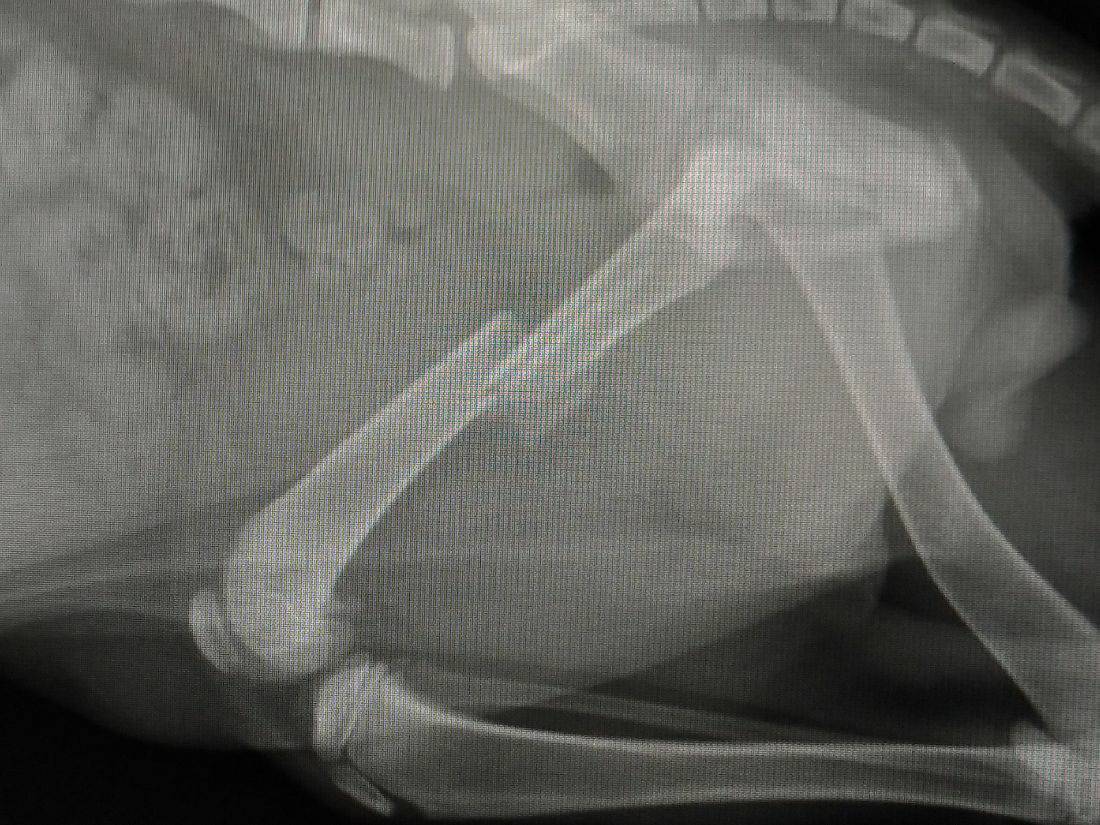

醫生初步看到X光片說小黑黑疑似橫隔赫尼亞,會先打針看看狀況,明天在拍一次X光片再研究是否確診,是否需要動手術,手術費用是一萬多。

而至於右後腿的骨折處,手術費也是一萬多,醫生有建議若醫藥費過高可以考慮只做赫尼亞,因為小黑黑是幼貓復原能力較好,會自行在受傷骨折處修復,只是以後走路會一跛一跛。

我比較擔心,小黑黑是幼貓,跛腳對浪貓影響會不會生存競爭力?抱歉,說很多,我是新手,不知道怎麼表達完整,謝謝您撥空閱讀,感恩!動物近況說明: 住院後確診為橫隔赫尼亞,右後大腿骨骨折,肝臟自橫隔破洞處滑入胸腔,壓迫大部份左肺,小部份右肺,肝臟並有發炎腫大現象,經醫生開刀處理及投藥治療後,左肺塌陷部份仍然沒有恢復,可能功能喪失,右腿骨折處由貓咪自體恢復,橫隔赫尼亞病況已經痊癒。